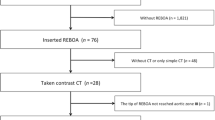

In total, 1354 non-trauma patients (694 females) were included after excluding 64 individuals because of various reasons (Table 1 & supplemental Fig. 1). Missing body height and weight data were computed for 264 patients (19.5%). Inter-observer reliability testing asserted there was no significant difference between the two measurers.